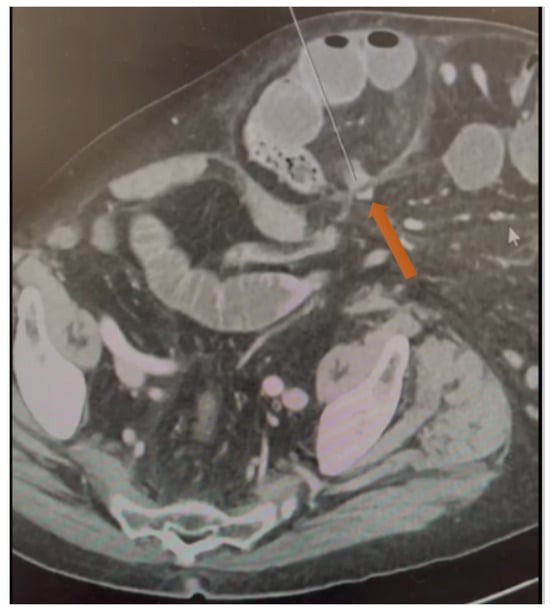

Figure 1.

Axial CT scan showing the neck of the hernia defect in the lateral abdominal wall at the level of the iliac spine see the orange arrow indicates the neck of the hernia.